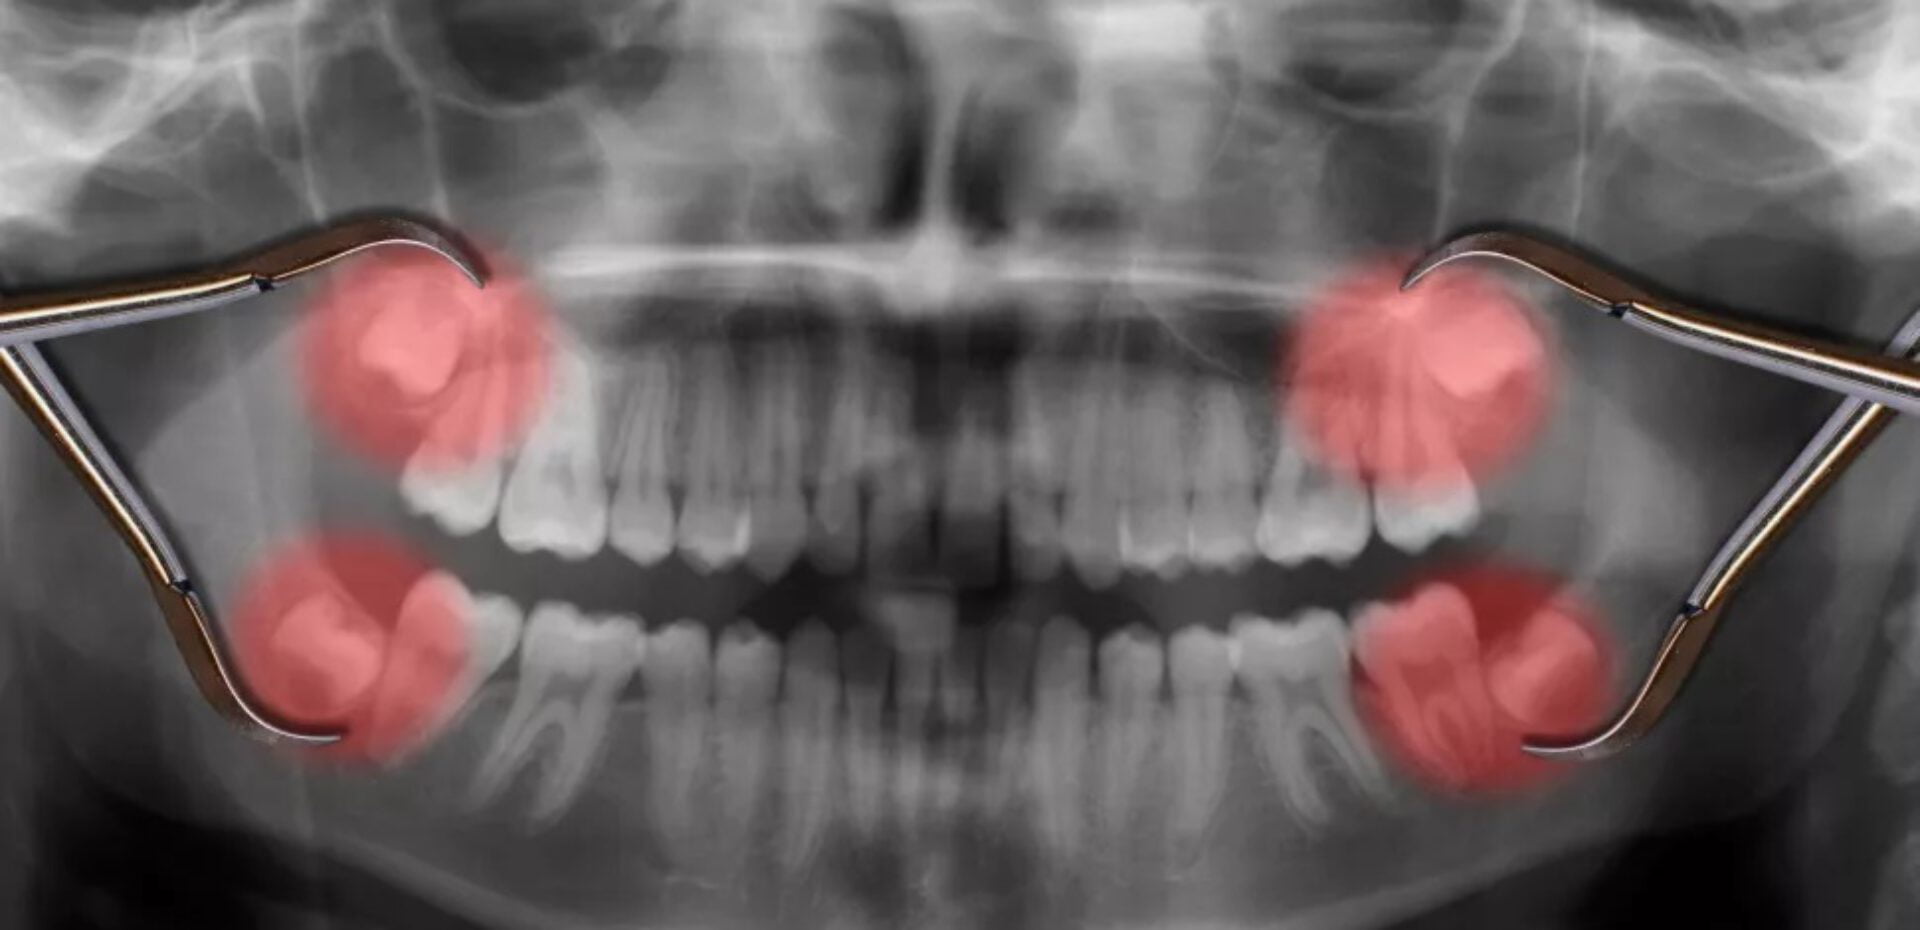

امروزه دندانپزشکان اغلب دندانهای عقل را میکشند، زیرا بیرون آمدن آنها میتواند باعث درد در بین شلوغی دهان و دندانها شود. حتی اگر فردی درد نداشته باشد، کشیدن این دندان در سنین جوانی میتواند از مشکلات سلامتی در مراحل بعدی زندگی مانند عفونت لثه جلوگیری کند. دندانپزشکان و جراحان دهان عموماً دندان عقل را به عنوان یک اقدام پیشگیرانه، به طور مثال در سن 27 سالگی خارج نمیکنند، زیرا خطرات مانند آسیب به اعصاب مجاور را افزایش مییابد. با این حال، افراد ممکن است پس از این سن، به دلیل مشکلاتی مانند درد، دندان عقل خود را بکشند بنابراین این اقدام هرچه زودتر صورت بگیرد بهتر است.